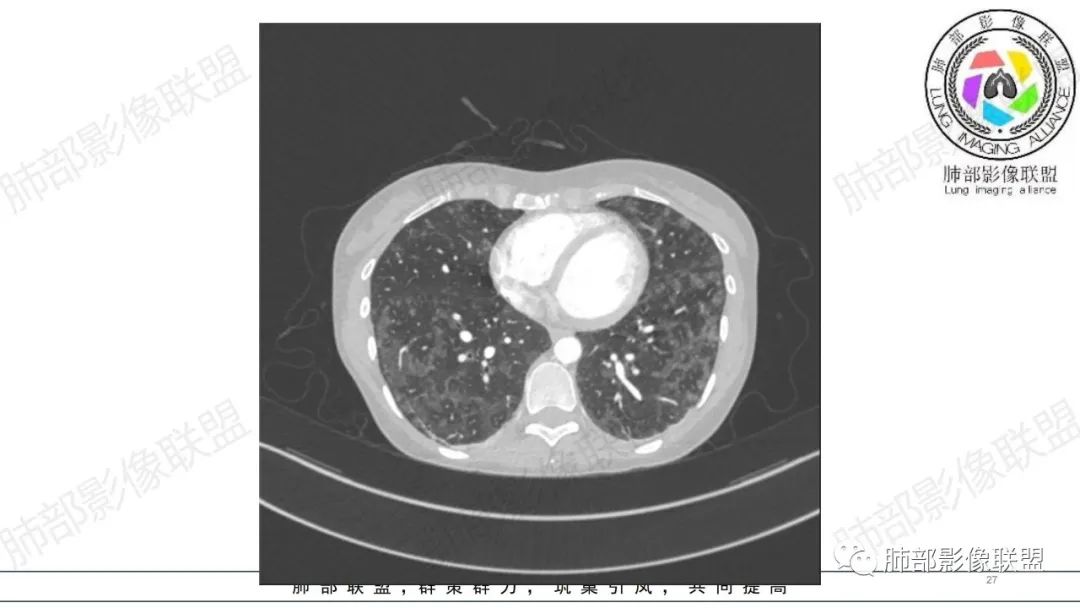

34岁女性患者,“哮喘”病史30年,近期有可疑刺激性气体吸入史;因乏力半年,咳嗽、憋气、发热4天就诊;6.1CT提示双肺广泛毛玻璃影及粟粒样结节,胸膜下闲置及血管周闲置,可见树丫征,部分小叶间隔增厚。考虑:1.过敏性肺泡炎,有可疑刺激气体接触史,胸膜下闲置,广泛毛玻璃影,地图样分布,粟粒结节边界模糊,支持过敏性肺泡炎,但糖皮激素治疗效果不佳,且动态复查血常规血红蛋白进行性降低,过敏性肺泡炎 不符合;2.肺含铁血黄素沉积症:患者30“哮喘”病史,可能为肺含铁症状,肺部CT提示双肺弥漫毛玻璃影及粟粒结节影,中下肺明显,肺底部分小叶间隔增厚,近期咳嗽、憋气、发热,血常规血红蛋白进行性下降,考虑肺含铁急性期症状,但临床无咯血症状,肺含铁不典型。综合考虑:肺含铁血黄素沉积症>过敏性肺泡炎。

年轻女性 ,急性喘息发热,肺部影像弥漫磨玻璃密度,部分细小腺泡结节,胸膜下黑线显示,短期复查,病变密度增高,下肺明显,血管周围肺组织累及较少、且逐渐成小叶间隔分布。考虑弥漫肺泡内病变,并经淋巴道转移,下肺比上肺明显,多为免疫细胞功能下肺较强。1.过敏性肺泡炎,有相关病史,三层密度特点、头尾测分布,符合。2 肺泡微石症,多有钙化,且缓慢起病,病程不太符合,放待排。3 吸入相关肺损伤,有病史,疾病演变过程也符合渗出-肉芽肿改变,建议详细询问病史。4 感染性病变,结核?病变气道分布为主,如此弥漫且没有树丫不符合。5.巨细胞病毒,可以磨玻璃 结节 改变,没有免疫缺陷病史。最后考虑吸入所致 1过敏性肺泡炎、吸入性肺损伤 鉴别肺泡微石症。

肺内气腔磨玻璃结节,肝脾肿大,治疗后间质改变,弥漫大B可能